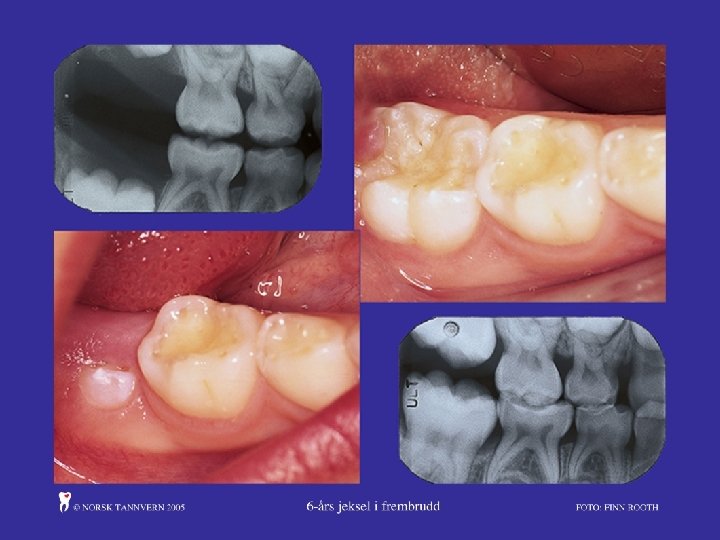

Hypomineralisering:

Råd om tannpuss og tannhelse 1. trinn: (evt. kan lege gjere dette ved skolestartsamtale) • Tannpuss med fluortannkrem to gonger dagleg • Ikkje skylje munnen etter tannpuss • Foreldre bør hjelpe barna med tannpuss eller overvake tannpussen til ca. 10 år • Når 6 -årsjekslane kjem er det viktig med god tannpuss på jekslane sine tyggeflater • Følg nasjonale anbefalingar om kosthald • Barn og foreldre bør spørjast om dei opplever problem med tenner eller munn og om barnet har vore hos tannlege eller tannpleiar. Tilvis om nødvendig. • Unngå mellommål og drikke tilsett sukker • Unngå hyppig inntak av syrehaldig mat og drikke, surt godteri og sitrusfrukt • Drikk vatn som tørstedrikk